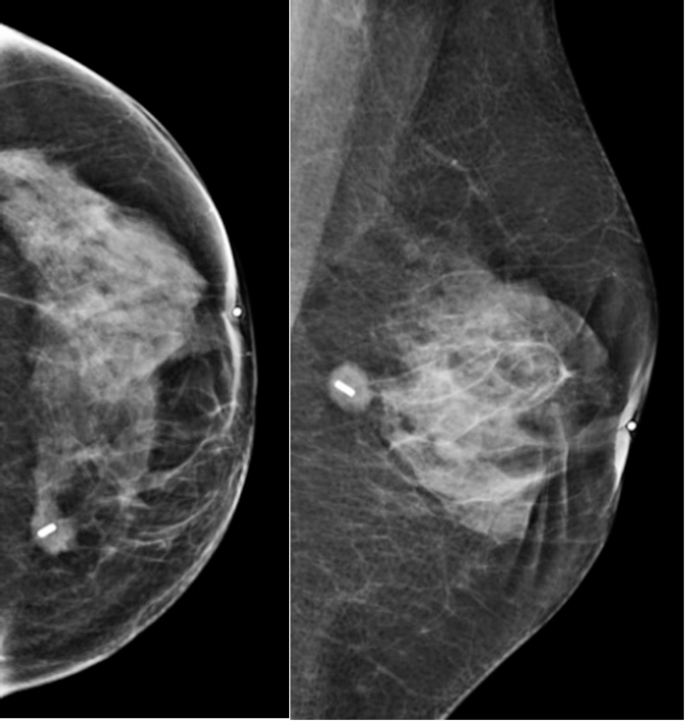

During the procedure, the marker location was confirmed repeatedly by regular probe guidance. The magnetic marker and the tumor excision were verified in two steps. Firstly, the location of the marker was confirmed within the excised specimen using the probe, and secondly, a specimen X-ray was performed immediately in the radiology unit (Fig. 2). Shaving of the cavity margins was decided upon by the individual surgeon, following review of the specimen X-ray.

Intra operative control of the excision of the tumor with the magnetic marker. The magnetic marker is correctly placed at the center of the tumor. A surgical clip is used on the 12o’clock axis to give the orientation of the tissue removed.